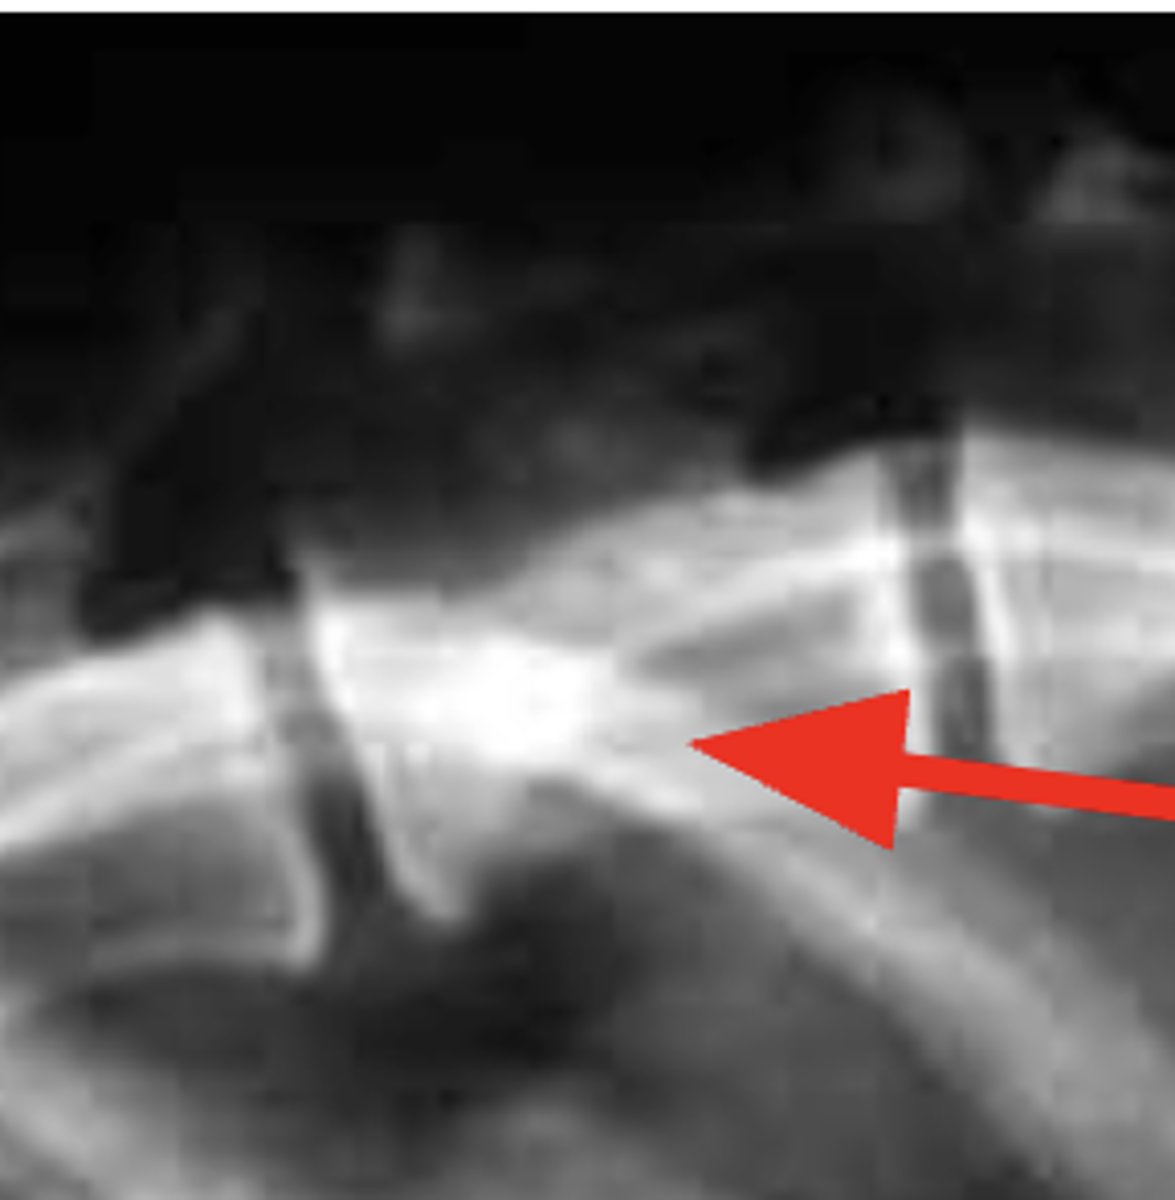

Tibial tuberosity

What anatomical location is indicated by the arrow?

What is the anatomical structure indicated?